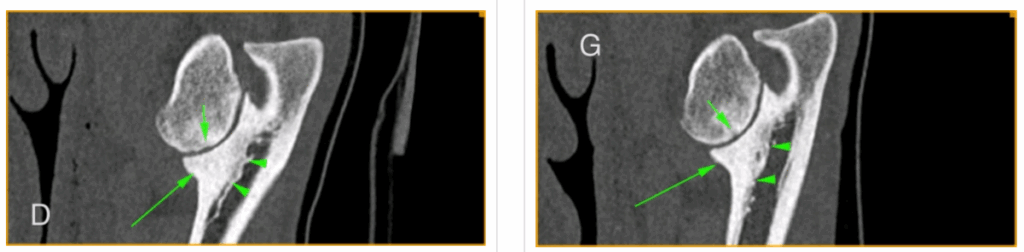

Le principe est le même : l’articulation du coude ne se développe pas correctement. Cela peut concerner l’une ou plusieurs des trois parties du coude (humérus = os du bras, radius et ulna = os de l’avant-bras).

Des fragments d’os ou de cartilage (qui recouvre l’os) peuvent se détacher, ou l’articulation devenir mal emboitée, créant douleur, inflammation et perte de mouvement.